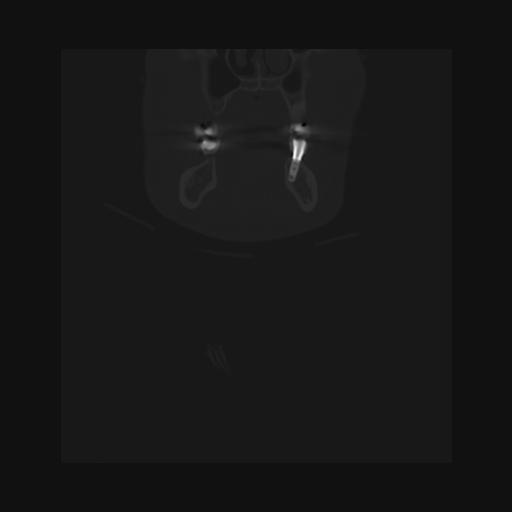

16 HUESO,,Coronal,2.000,HUESO,Coronal,